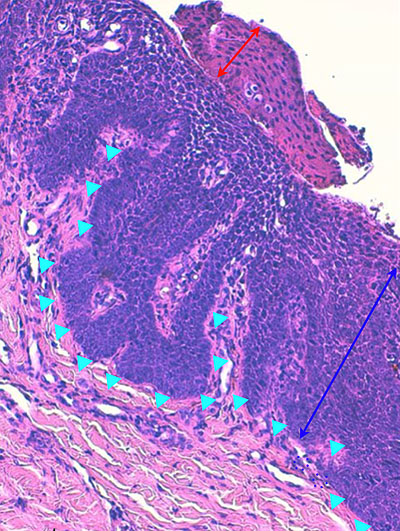

Photo 4 (Hémalun Eosine X 100) : aspect bleu de l’épiderme pour hyperplasie des couches basales, qui dessinent des crêtes épithéliales allongées, filiformes, ramifiées et branchues, peuplées de cellules basales hyperbasophiles. L’épiderme est multifocalement exulcéré. L’infundibulum folliculaire visible présente une hyperkératose parakératosique sans visualisation nette d’une couche des grains. Le derme montre une discrète angiectasie des capillaires du plexus superficial ainsi qu’un discret infiltrat inflammatoire périvasculaire superficial.

Légendes de la Photo 4 :

- Triangles bleus foncés : contours de crêtes épithéliales allongées, filiformes, ramifiées et branchues, peuplées de cellules basales hyperbasophiles.

- Triangles bleus clairs : exulcération épidermique

- Flèche rouge : parakératose épidermique et folliculaire

- Étoile rouge pleine :Le derme est faiblement à modérément inflammatoire (infiltrat mononucléé)

- Étoile rouge creuse : angiectasie des capillaires sanguins

- Étoile bleue claire : glandes sébacées

Photo 5 (Hémalun Eosine X 200) : ces crêtes épithéliales tout à fait particulières

(allongées, filiformes, branchues) peuvent également être présentes dans les couches les plus basales

de la gaine épithéliale folliculaire externe des infundibula folliculaires.

On note également l’aspect parakératosique diffus des infundibula folliculaires.

Légendes de la Photo 5 :

- Triangles bleus : contours de crêtes épithéliales allongées, filiformes, ramifiées et branchues, peuplées de cellules basales hyperbasophiles, émanant de la gaine épithéliale externe des infundibula folliculaires

- Flèches rouges : parakératose épidermique et folliculaire

- Étoiles rouge pleines : Le derme est faiblement à modérément inflammatoire (infiltrat mononucléé)

- Étoiles rouge claires : angiectasie des capillaires sanguins

- Ronds marrons : tiges pilaires